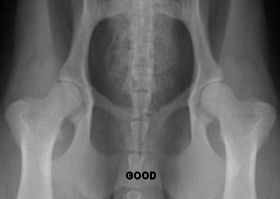

Below are hip x-rays of Cavaliers showing most of the grades of

classification. I don’t have a copy of a Borderline or a Severe.

You can find examples from other breeds online if you are

interested. You can easily see in each x-ray how there is less

and less coverage of the head of the femur (the femoral head—the

round ‘ball’ at the ‘top’ of the leg bone) and the acetabulum

(the ‘cup’ where the femoral head sits) gets more shallow as the

status of the hips declines until they barely overlap at all. In

a severe there is basically no overlapping whatsoever.